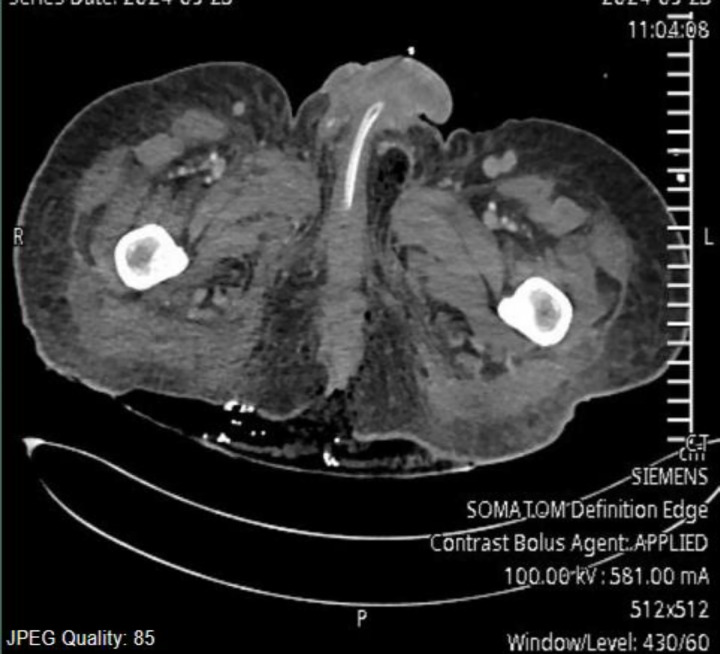

Case presentation: A 45-year-old male patient was admitted into the surgical intensive care unit with Fournier's gangrene, septic shock, and acute kidney injury (AKI). The patient was managed by invasive ventilation, noradrenaline, vasopressin, and renal replacement therapy. He developed Escherichia coli bacteremia and candidemia. We added meropenem and antifungal to the therapy. The transthoracic echocardiography showed EV vegetation and thread-like vegetation in the right coronary sinus, which was confirmed with transesophageal echocardiography. With aggressive therapies, the patient recovered from septic shock, organ dysfunction and was successfully liberated from invasive ventilation. The patient was discharged home on day 27. The antibiotics and antifungal were continued for 6 weeks. Two weeks after discharge, the follow-up echocardiogram was normal, and he was doing well.